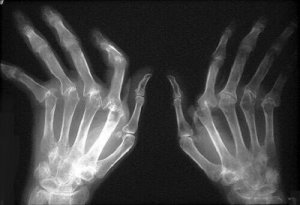

Głównym i najbardziej widocznym objawem choroby jest obrzęk lub zapalenie stawów. Są to objawy, które sprawiają wiele bólu. Obszary ciała, których najczęściej dotyka reumatoidalne zapalenie stawów to nadgarstki, łokcie, ramiona, palce u rąk i nóg, biodra, kostki i kolana.

Mogą się również pojawić guzki reumatologiczne, które są zgrubieniami występującymi na skórze (szczególnie po zewnętrznej stronie dłoni i stóp) lub wewnątrz ciała. Kiedy choroba przechodzi w stadium zaawansowane, w miejscu stanów zapalnym pojawia się deformacja stawów.